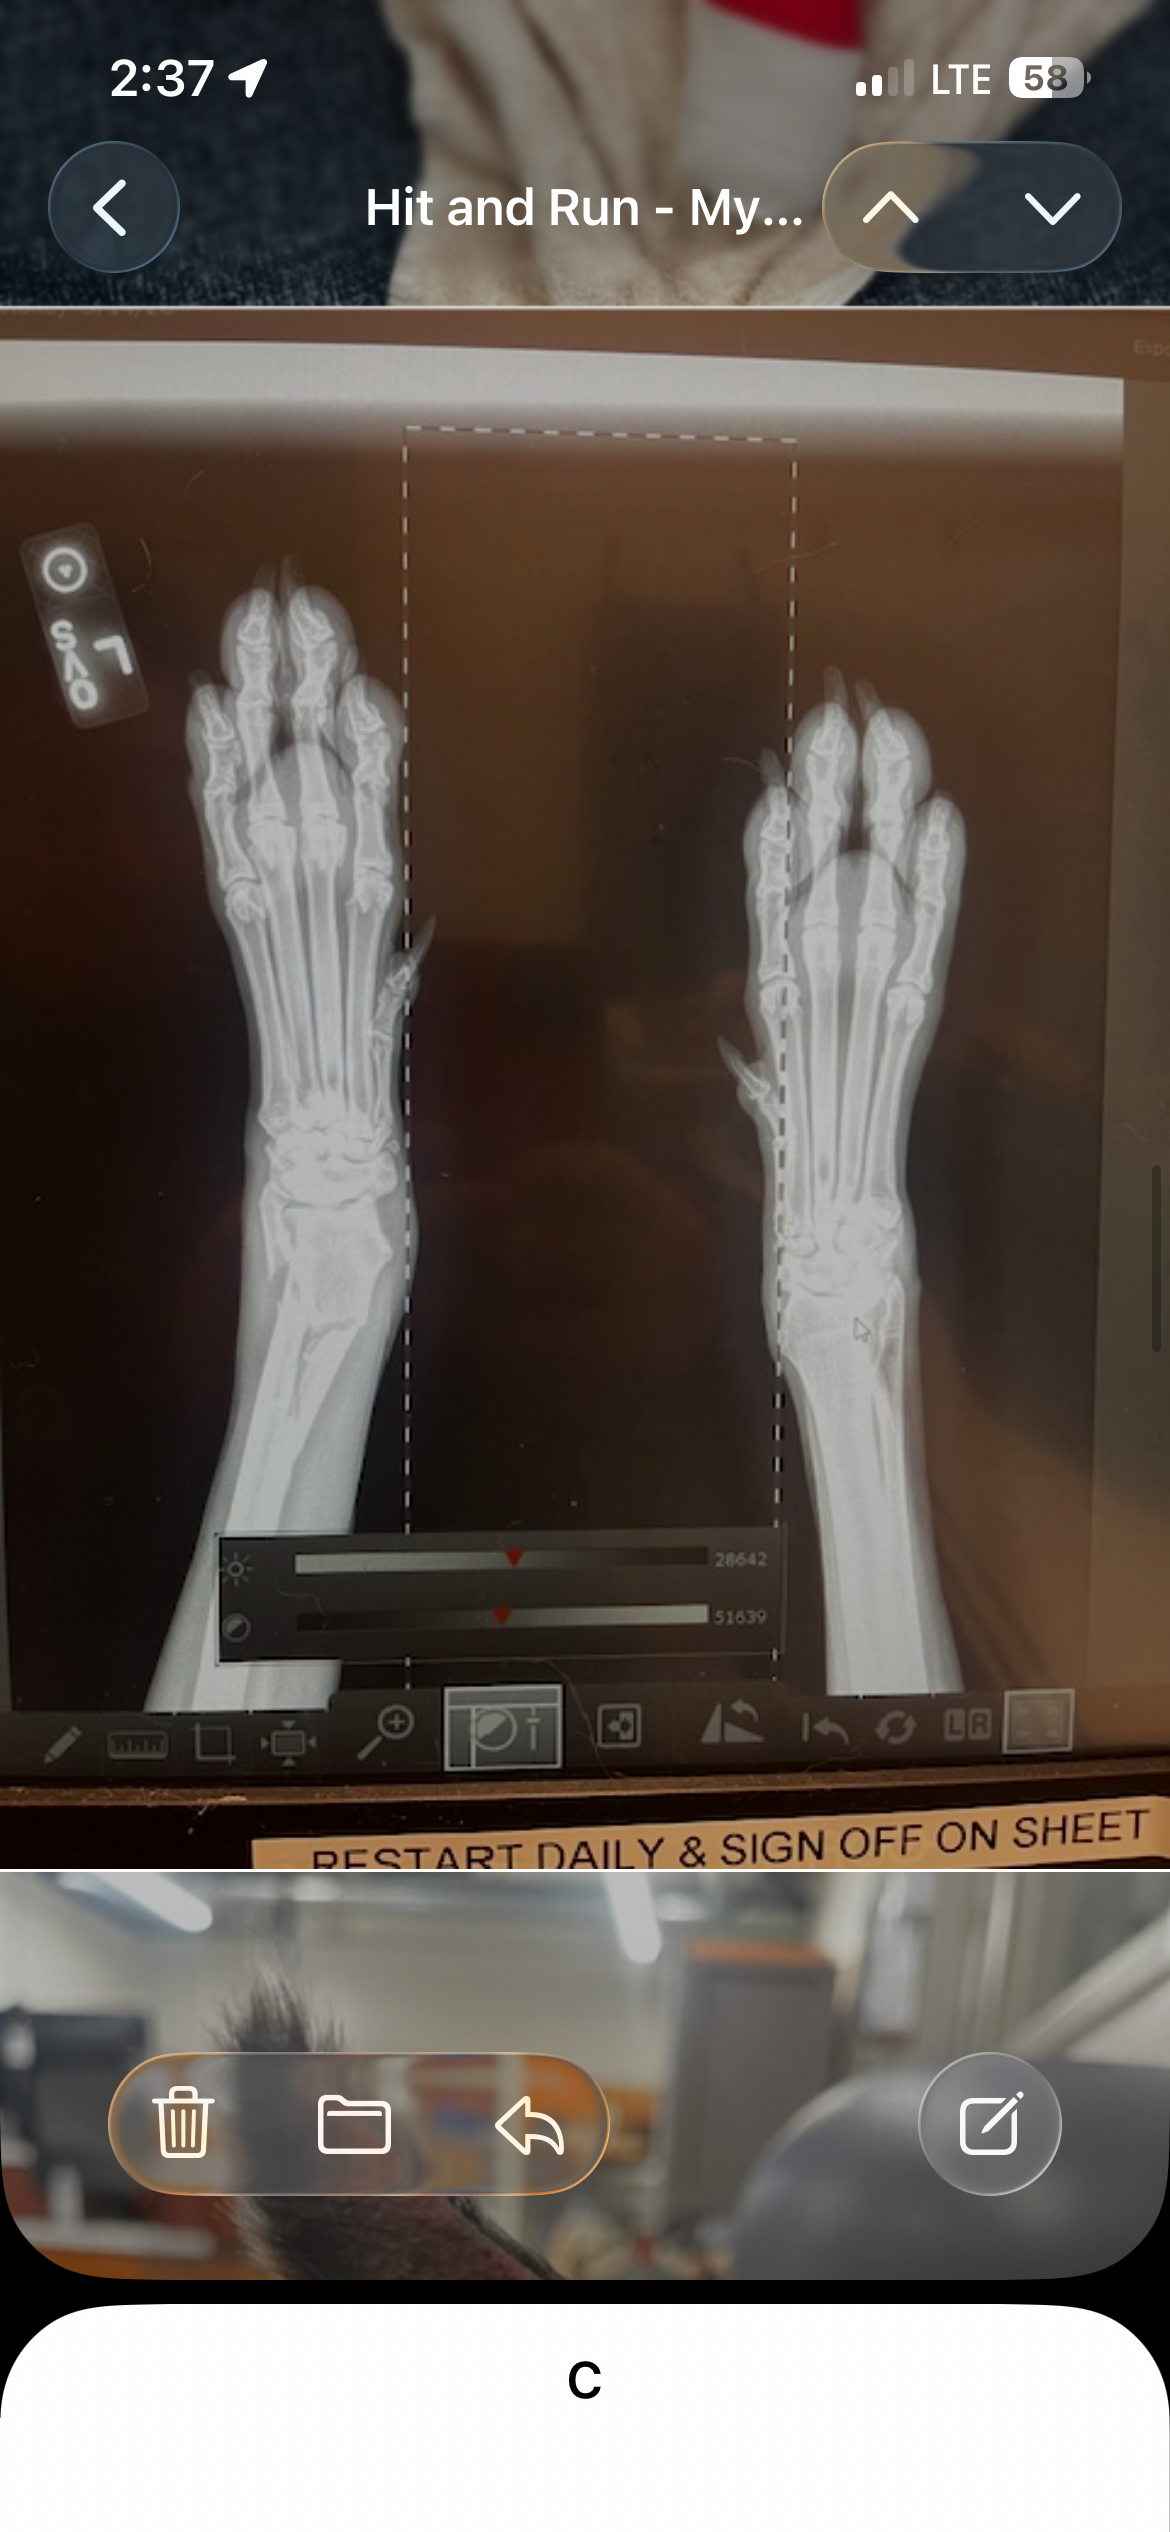

Sadly, everything changed in an instant. Lotus was recently hit by a car, and the person responsible fled the scene without stopping to help. In that moment, she was left injured, scared, and in unbearable pain. It’s something no animal should ever have to endure. Watching her go through this has been one of the most painful experiences of my life. The shock, the fear, and the helplessness I felt in that moment are something I will never forget. After rushing her for medical attention, we discovered that Lotus suffered a serious fracture in her left front leg, just above the wrist. It’s a critical injury that requires urgent

and specialized care. For a dog like Lotus—strong, active, and full of life—this type of injury is devastating. She can no longer move the way she used to. The simple things she loved, like running, playing, and even walking comfortably, are now painful challenges. The veterinarians have recommended immediate surgery at UC Davis Veterinary Hospital, where experienced specialists can properly repair her leg. This procedure is essential to give her the best chance at a full recovery. Along with the surgery, there are additional costs for diagnostics, medications, hospitalization, post-operative care, and rehabilitation therapy. Each step is crucial to ensure that her leg heals correctly and that she regains her strength and mobility. The funds raised through this campaign will go directly toward covering all of these medical expenses. This includes the surgical procedure, pain management, medications, follow-up appointments, and the rehabilitation process that will help Lotus learn to use her leg again.